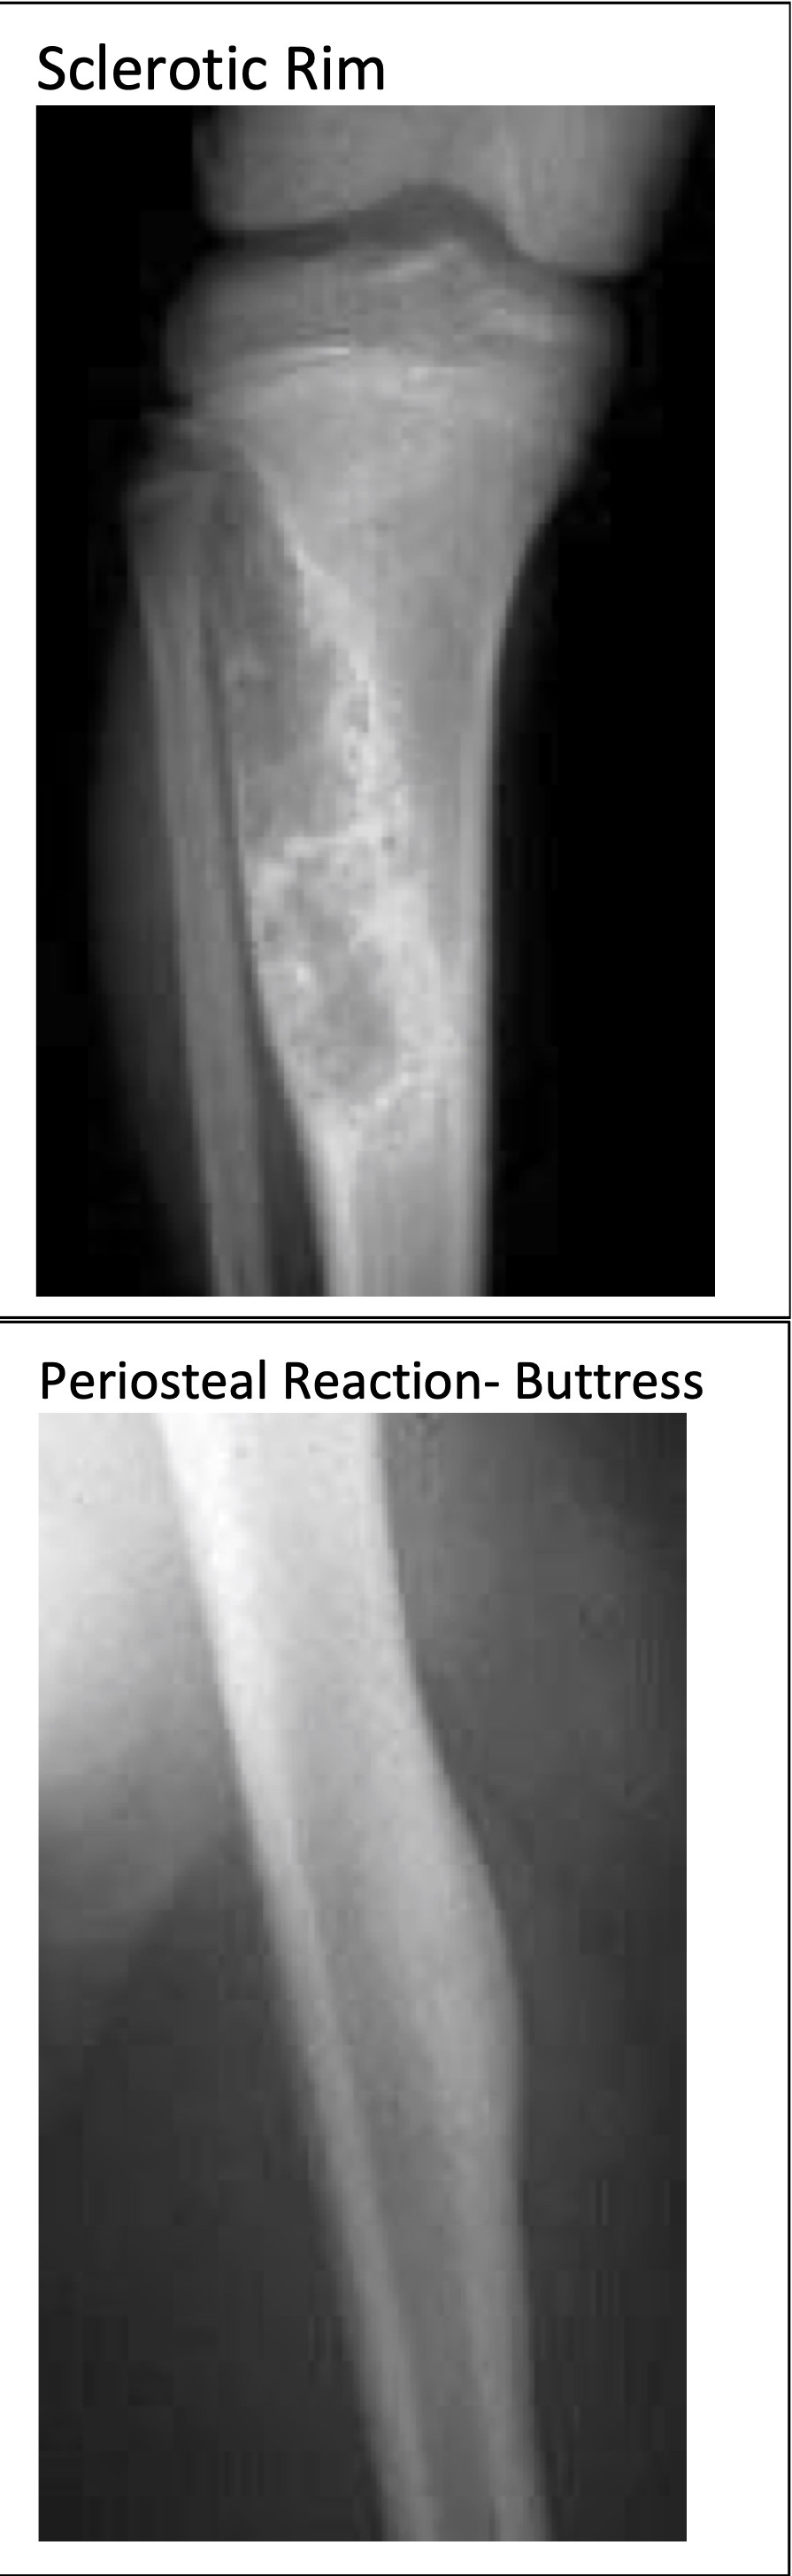

Periosteal Reactions

Benign and Non/Slow-Growing

Lesions

Rapidly Growing